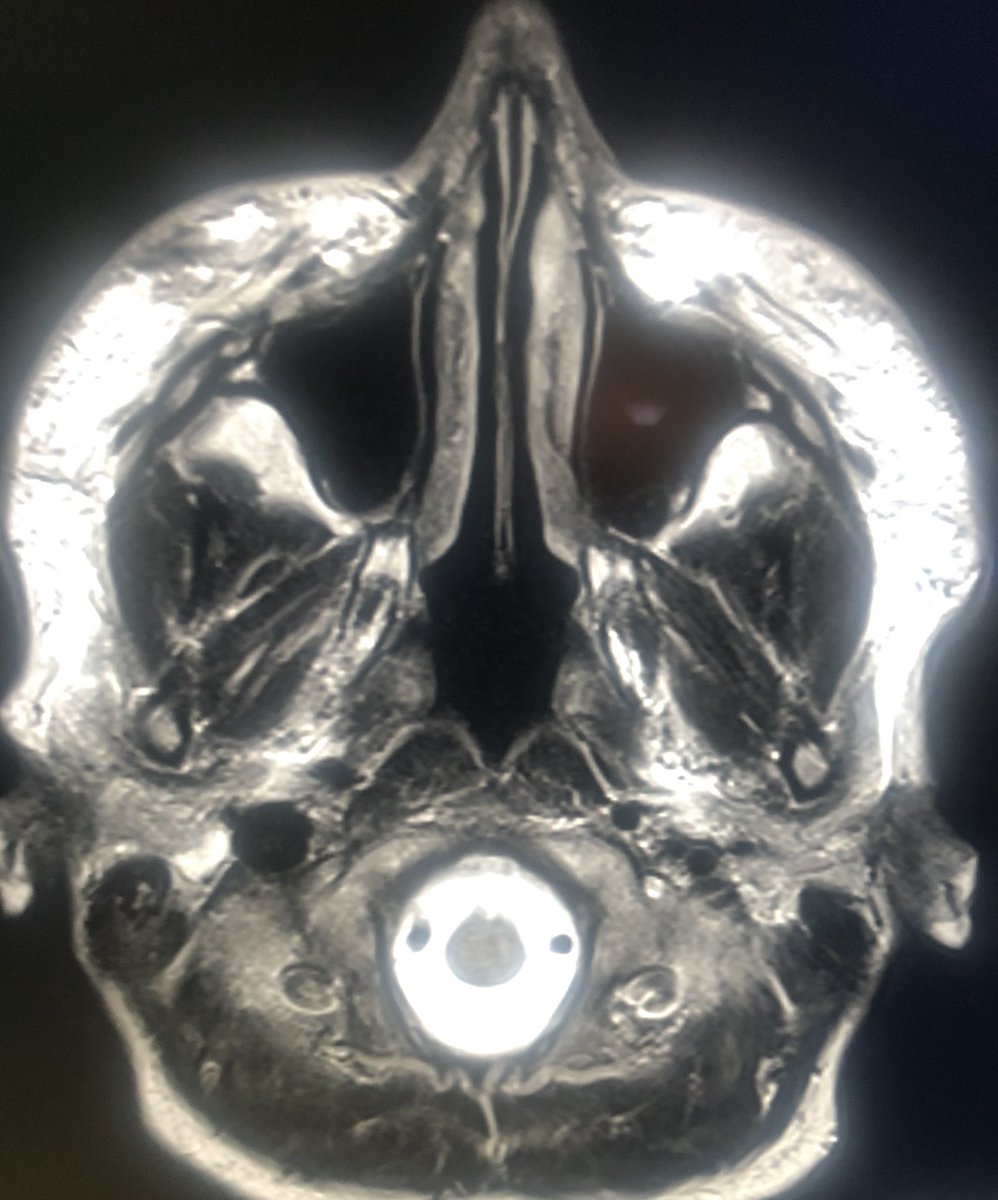

30 year old scanned for headaches. What do you all think?